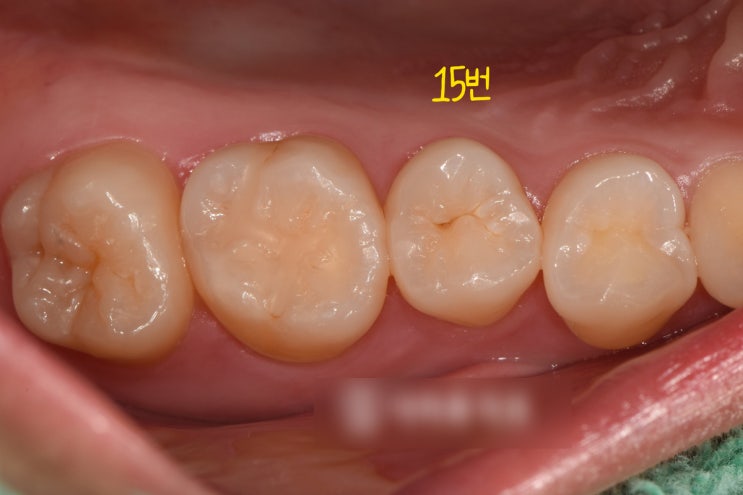

치아 충치 확인, 인레이 치료 과정, 치성 상악동염 임플란트 수술 서대문구 치과

안녕하세요, 대표원장 조민기입니다. 아래턱과 다르게 위턱뼈 속에는 빈 공간이라 부를 수 있는 거시 공간...